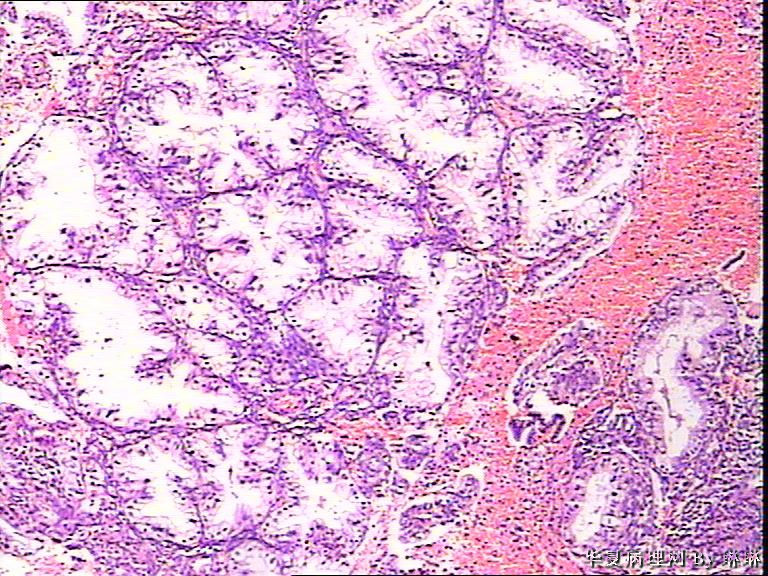

患者女性,38岁,月经量多4个月,曾服用止血药物,无其他病史。

开始临床没有提供怀孕的病史,后来我们有咨询临床科室,大夫还是说没有用药、月经正常,刚过了经期,月经量多,这次月经持续时间长入院。所以我们开始排除了高度分泌的A-S反应,看到腺体增生呈乳头状,还有异型性,而且镜下部分子宫内膜还有增生期改变的,不完全是高度分泌的。再三考虑后还是要求临床查了血HCG,结果显示HCG370多。最后我们发了单纯性增生伴高度分泌。

晚泌期宫内膜,并见A-S现象

腺体呈高度分泌反应,我们必须结合病史,考虑是否药源性反应,或持续黄体期子宫内膜.

A-S反应

复杂性增生伴分泌反应

A-S反应?